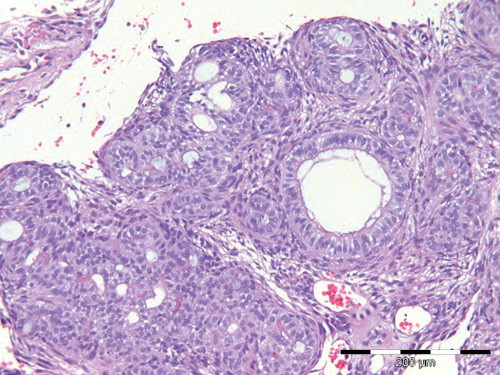

Histologisk er AOT en cellerik tumor med kjertel-lignende strukturer, hvilket har gitt svulsten sitt navn (figur 1 og 2). Der er kubiske celler som er organisert som utførselsganger og små rosetter som kan minne om kjertel-elementer. Gangstrukturene har kubiske celler med kjernen polarisert bort fra lumen. Tumor er omgitt av et modent og løsmasket bindevev, og der er rikelig med blodkar. I mange tilfeller er det henfall av vev, slik at man får inntrykk av cysteutvikling.

Figur 2. Kasus 3: Nærbilde der gangstrukturene kommer tydeligere frem. Tumor er rikt vaskularisert og har et modent bindevev. Målestav 200 m.